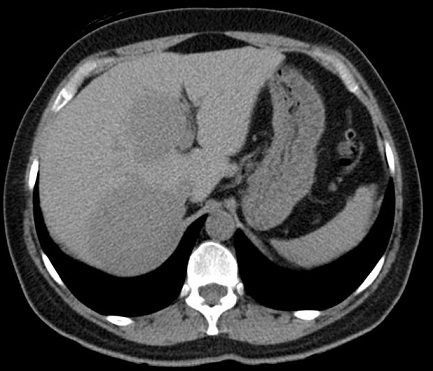

Image TDM de kyste du

foie : Image lesionaire arrondie , de taille variable souvent de

quelque centimetrique . Densite liquidienne de 0

a 15UH

Image radiologique TDM d'une kyste simple

du foie droit en coupe axiale : Aspect

lesionnel a densite variee de 7-15 UH ( hypodense )

avec bord lisse , bien definie et regulier |